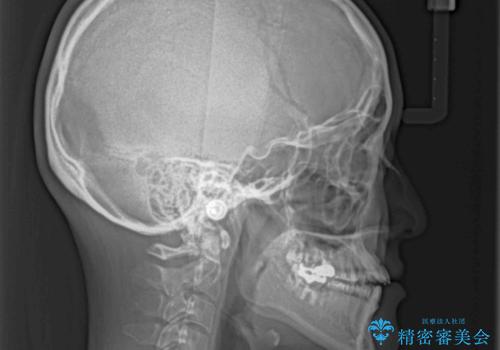

開咬の治療は、前歯を閉じるように動かすとともに、上下臼歯を圧下(骨内にめり込ませる)させることで進めて行きます。

インビザラインは臼歯の圧下を効果的に行えるため、インビザラインを用いて矯正治療を行うこととしました。